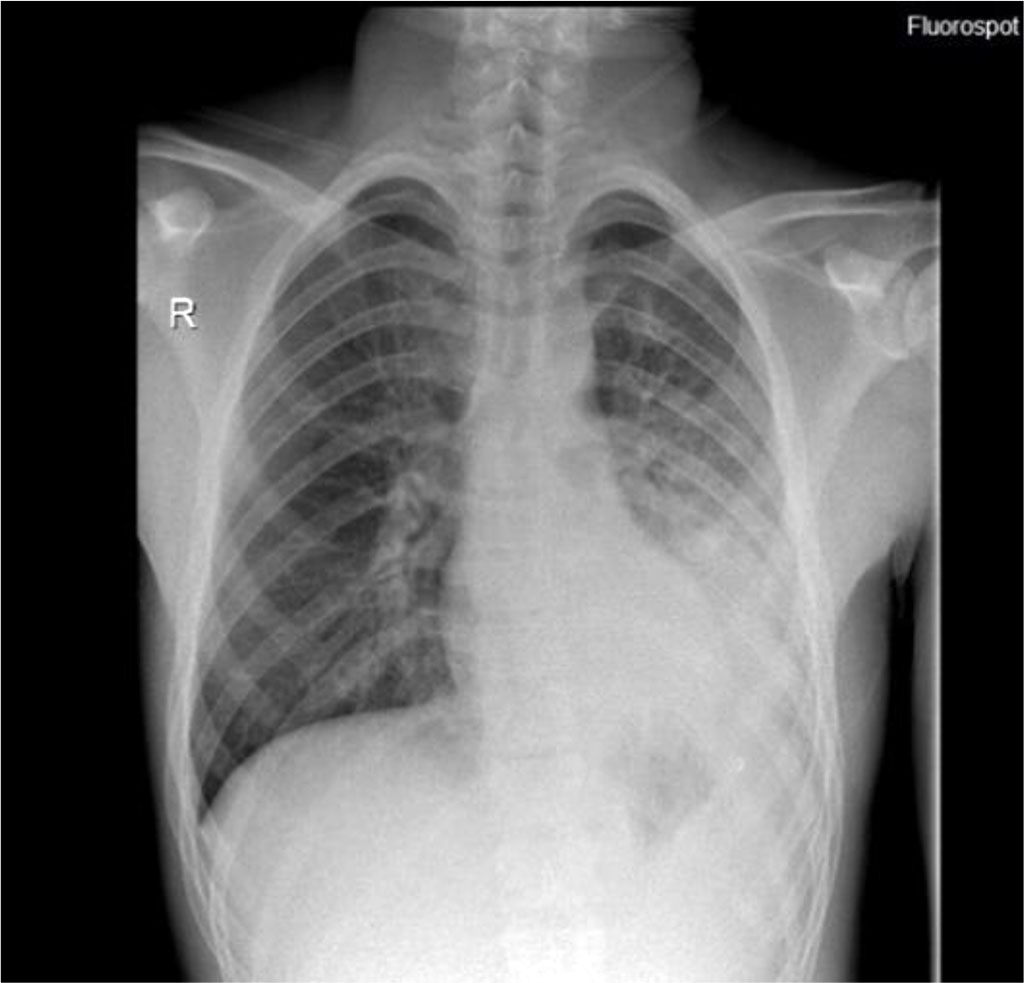

A number of additional paraclinical examinations were recommended for the diagnosis: sample of tracheobronchial aspirate, nasal exudate, haemoculture, urine culture, coprocytogram and stool culture, but all these do not lead to a specific etiological factor. Ac VHC, Ag HBs, Ac anti Mycoplasma pneumoniae IgM, Ac anti Borrelia burgdorferi IgM, Ac anti Cytomegalovirus IgM, Anti-HIV 1+2 were negative. Front-rear thoracic X-ray reveals a medium-intensity dull structure, unclearly delimited, without the aerial bronchogram visible in the lower half of the left hemithorax, with moderate attraction effect of the lateral intercostal areas (figure 1).

Figure 1. Thoraco-abdominal X-ray - dull structure unclearly delimited in the

left hemithorax.

Source: Authors' own work